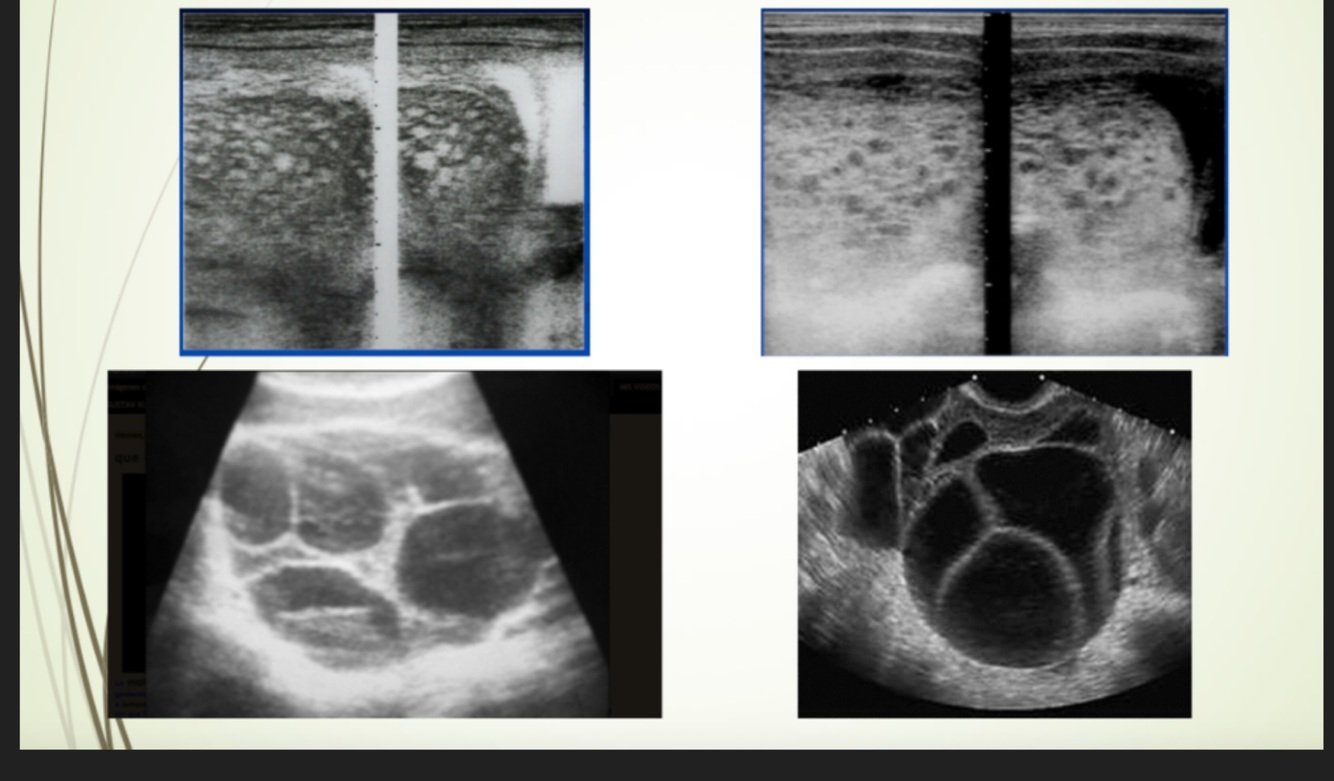

Masculino de 56 años, olor y aumento de volumen testicular, imagen de USG

A

Hidrocele

Femenino de 34 años, FUM hace 14 semanas

Embarazo múltiple

Femenino de 42años

FUM hace 8 semanas, USG

Mola Hidatiforme